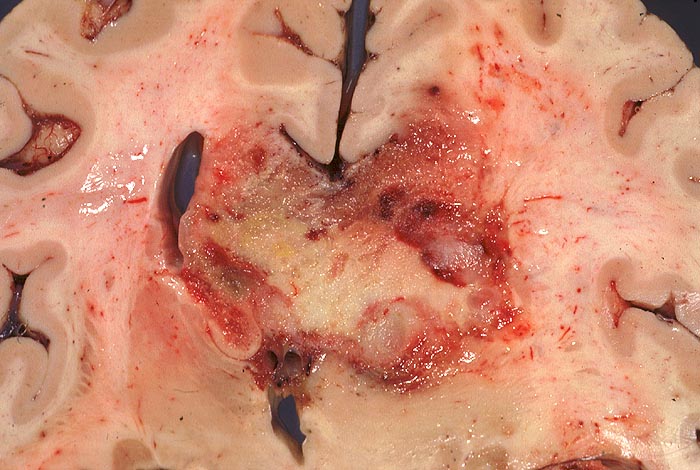

PathoPic ID 946 - Glioblastoma multiforme

Glioblastoma multiforme

maligner Tumor

Hirn parietal

Nervensystem

Bunter unscharf begrenzter schmetterlingsförmiger Tumor. Der Tumor überschreitet die Mittellinie im Bereich des Balkens und infiltriert beide Hemisphären. Intraventrikuläre Tumorausbreitung rechts.

Makroskopie